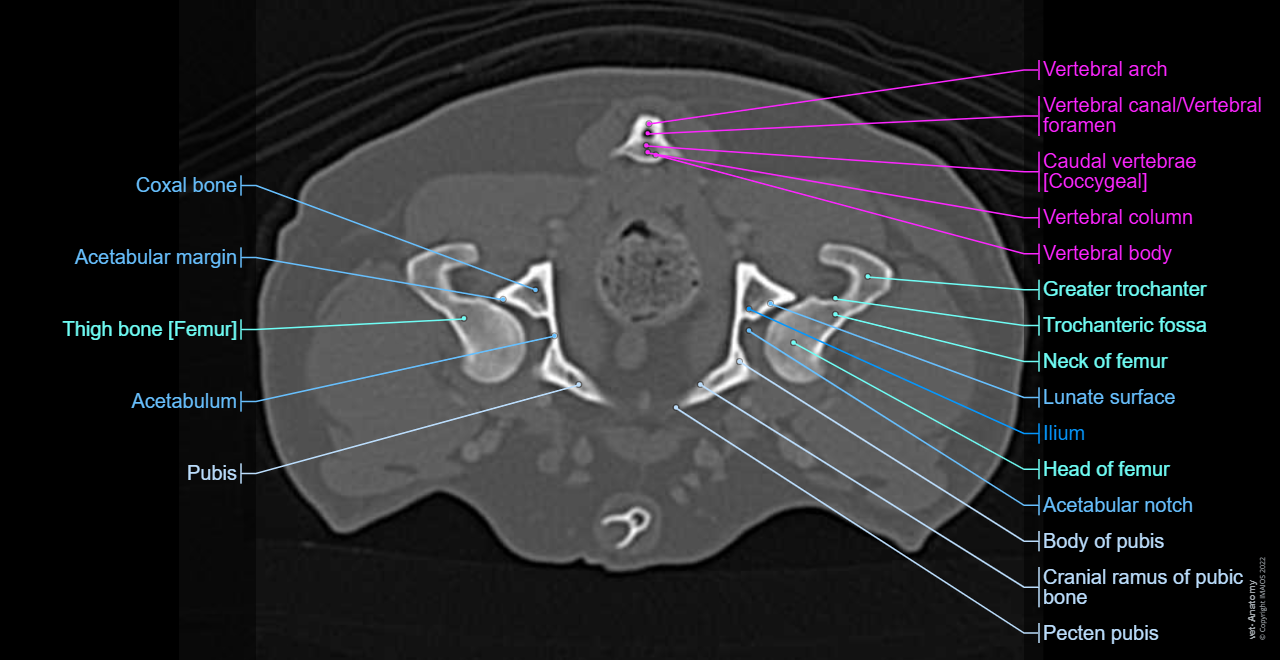

Dog - Coxal bone - Penile bone [Baculum]

Dog